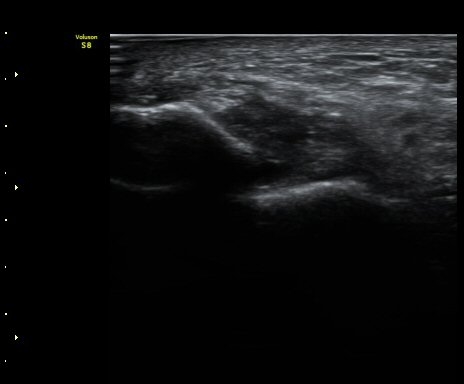

Á¾µ¹ºñ°ñÀδë Á¾´Ü¸é°Ë»ç¿¡¼­ Á¾°ñºñ°ñÀδë´Â Á¤»óÀûÀÎ ¸ð¾çÀ¸·Î °üÂûµÈ´Ù(±×¸² 3, 4).